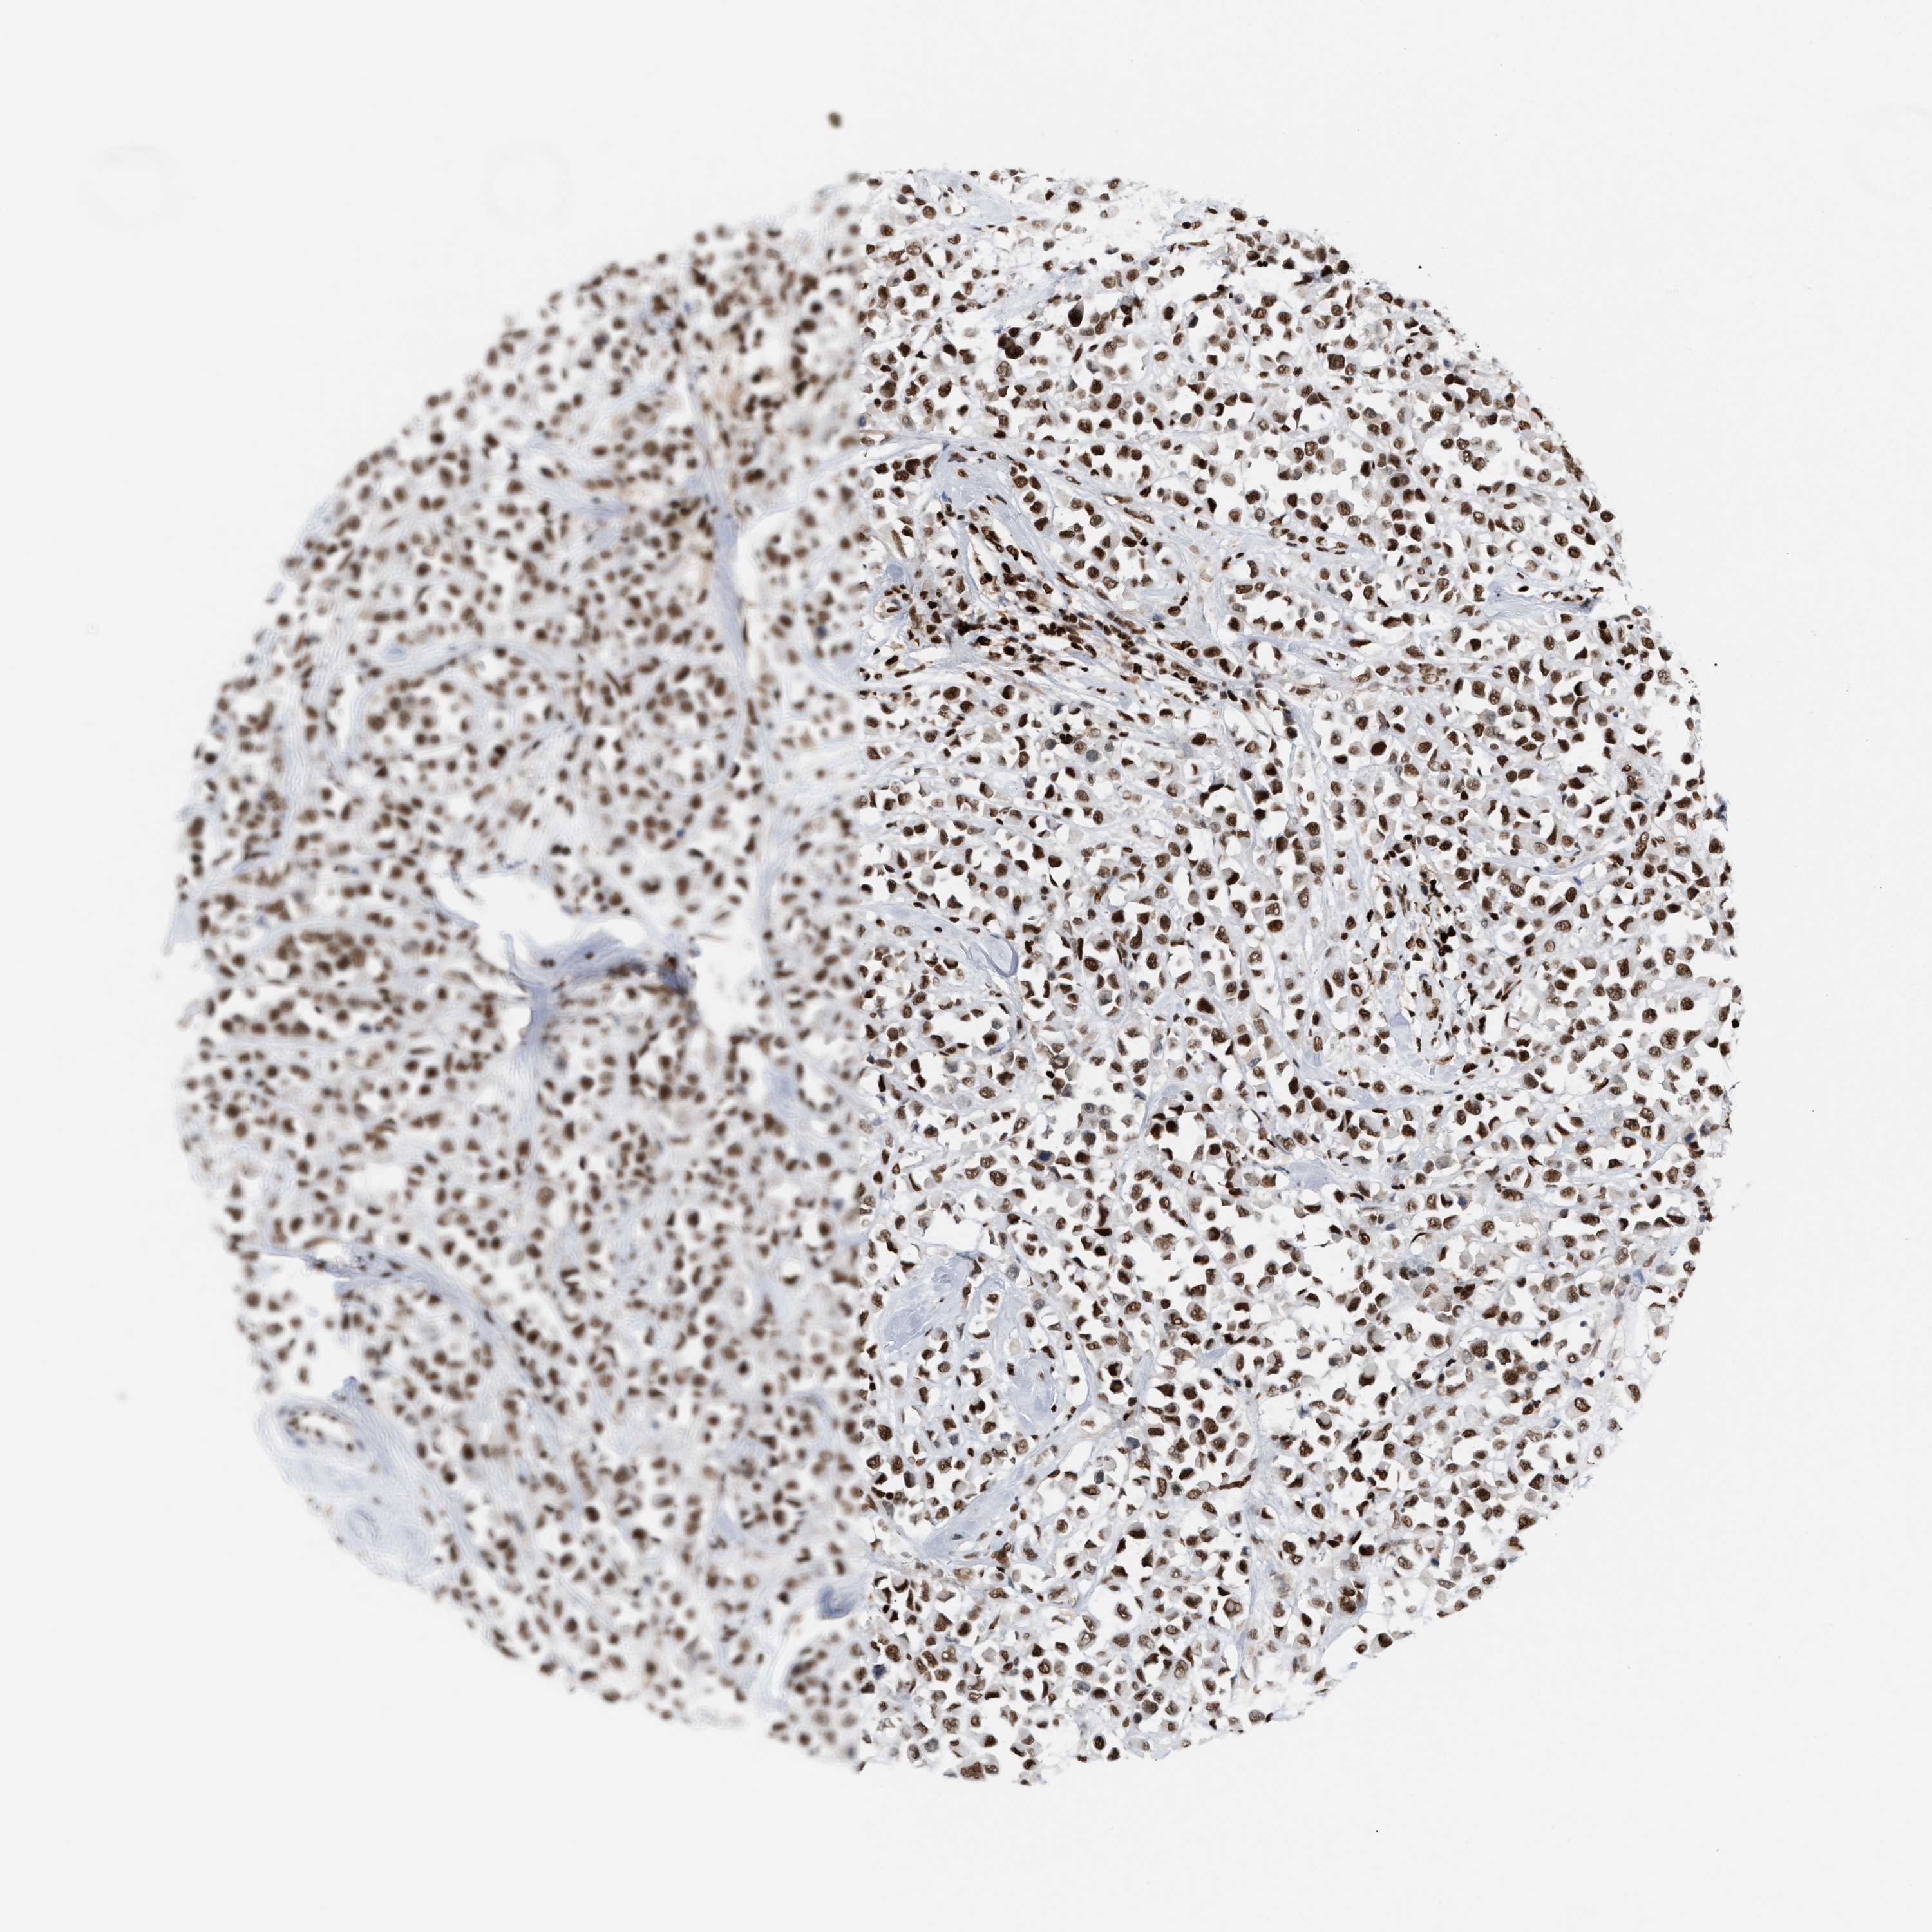

CANCER BREAST CANCER Show tissue menu

BRCA TCGA BRCA VALIDATION PROTEIN EXPRESSION

ANTIBODIES

AND

VALIDATION